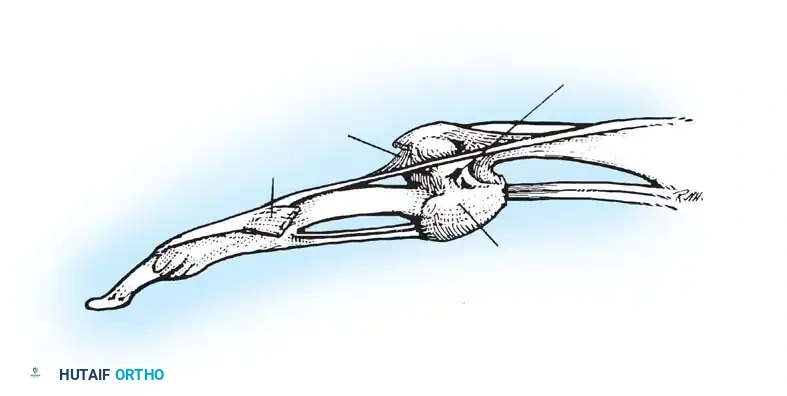

Fig. 70-11 The Bunnell test for intrinsic tightness. Extension of the MCP joint exacerbates PIP extension forces if the intrinsics are contracted.

Surgical Warning: With ulnar drift of the fingers, intrinsic tightness may be present only on the ulnar side. To test this accurately, axial alignment of the finger with the metacarpal must be maintained. Any ulnar deviation at the MCP joint during the test slackens the intrinsics on the ulnar side and will yield a false-negative result.

A tight first volar interosseous muscle pulls the extended index finger ulnarward. If the finger is held in line with the second metacarpal during the test, tightness of this specific muscle can be isolated. The first volar interosseous is a flexor and adductor of the second MCP joint, whereas the first dorsal interosseous is typically an abductor only.